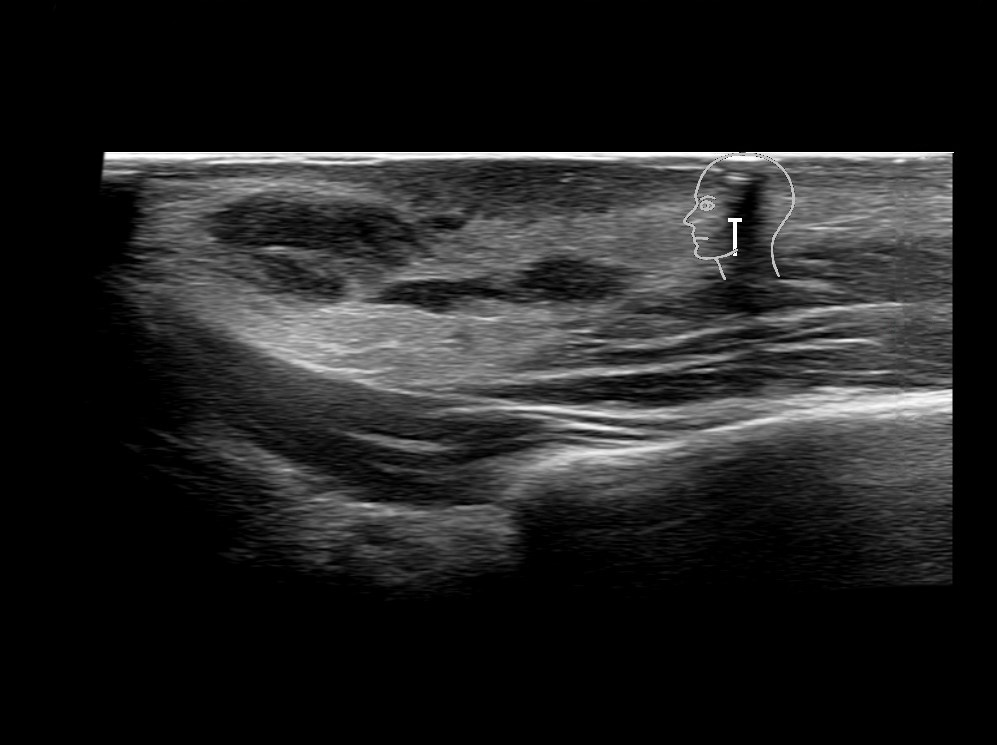

Filler injections in the parotid gland may go unnoticed, however, inflammatory reactions and abscesses may occur. Hypervascularity can be seen with color doppler. Filler deposits are supposed to be injected into the superficial fatty layer . The space to inject into this layer may be limited. Routinely we measure a width of 2-4 millimeters with sometimes subcutaneous layers being less than one millimeter thick.

Study the first image to recognize the different layers. If you are sure about the layers, swipe to the second image to view the answer (if applicable).